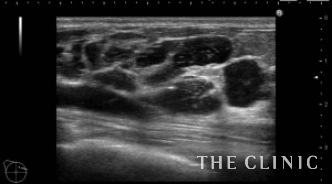

この方は2ヵ月前にヒアルロン酸注入を受けられていますが、除去したいとのご希望でご来院されました。エコーにて、乳腺下に一塊のものと蜂の巣状、皮下にも蜂の巣状のヒアルロン酸のしこりを確認しました。

しこりを穿刺し、ヒアルロニダーゼを注入して吸引除去します。